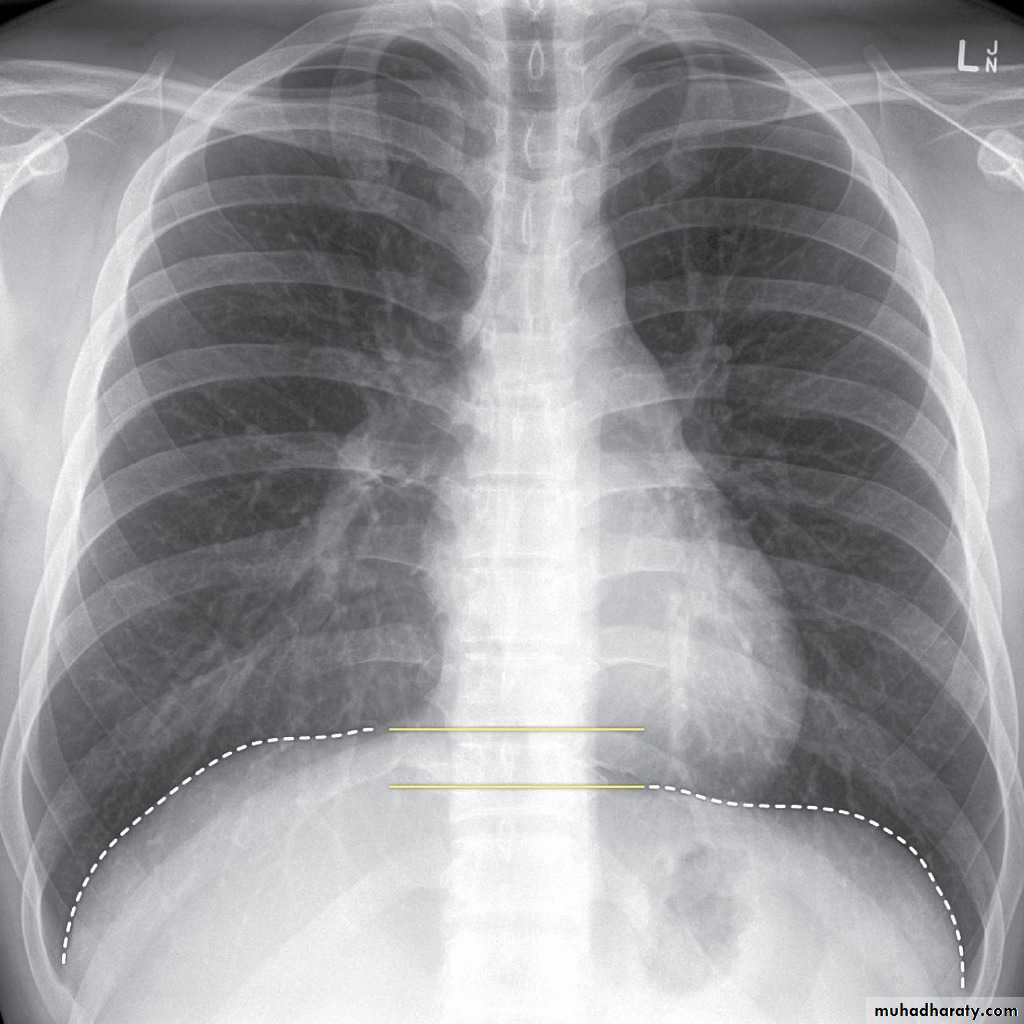

CXR of adult male PA and lateral views, it shows :Normal both lung fields ,Central cardiac shadow, Central trachea, central mediastinum, No boney lesions, no soft tissue abnormalitiesnormal radiologic anatomy of the chest Look carefully on both diaphragmatic cruse costo & cardio phrenic angles. Useful in detection of pleural effusion

Upper zone>>>> 1st and 2nd ribsMiddle zone>>>> 3rd and 4th ribsLower zone>>>> 5th and 6th ribsHow to asses cardiac size We take 2 lines the between borders of cardiac shadow and 2 lines between the inner surface of thoracic cage and the ribsCardiothoracic ratio (CTR) =Cardiac Width : Thoracic WidthA CTR of greater than 1:2 (50%) is considered abnormal.